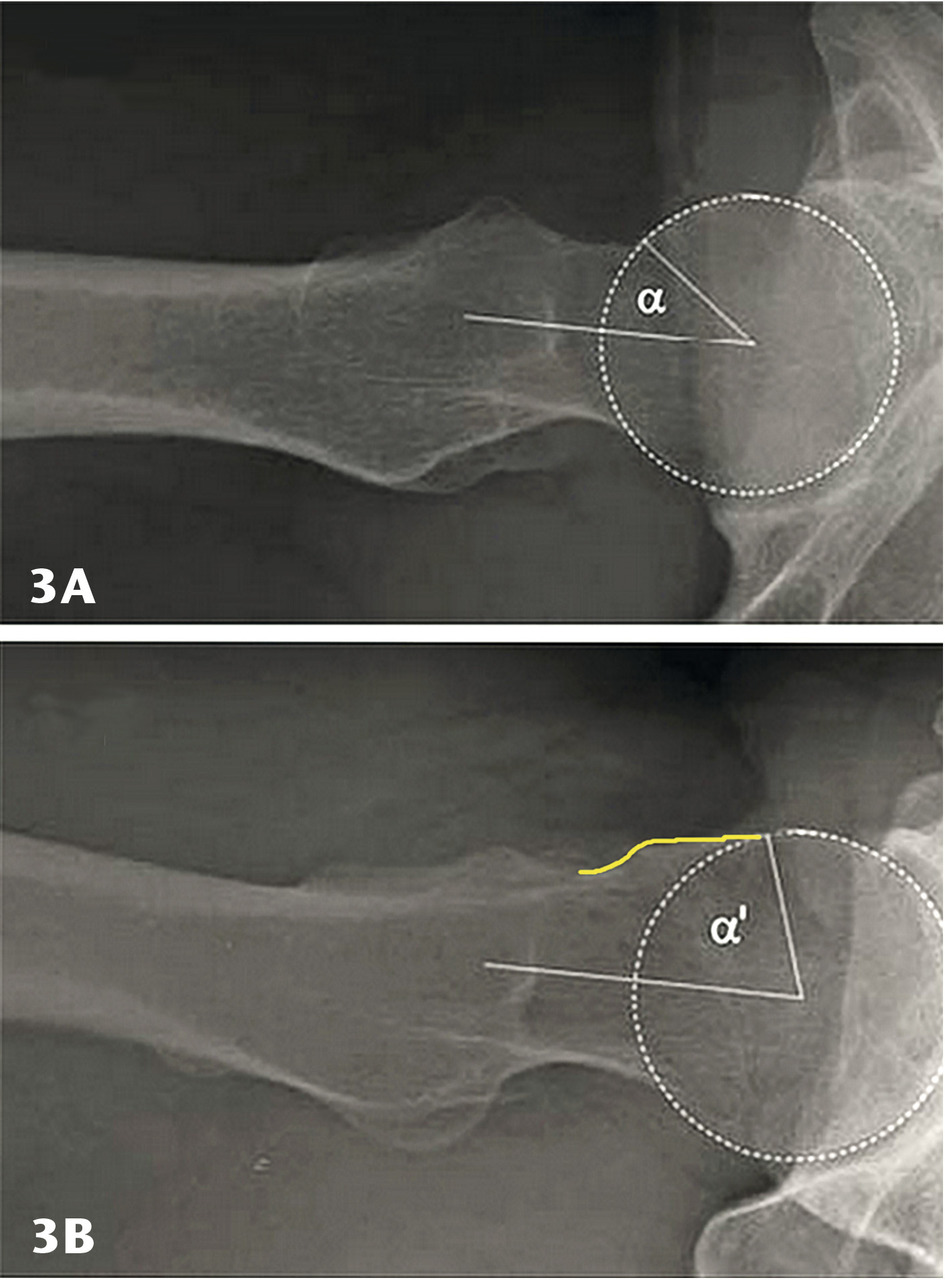

Les radios standard comportent des clichés du bassin, face et profil (bassin de face debout en charge). On peut voir un effet pince avec une éventuelle rétroversion acétabulaire, une coxa profunda avec protrusion acétabulaire. L’effet came est recherché en incidence spécifique : le profil de Dunn à 45°. Il déroule le col fémoral pour mettre en évidence sa « bosse » et la perte de sphéricité de la tête (fig. 3). On peut ainsi calculer l’angle alpha, norma-lement inférieur à 50°. Au-delà de 50°, il y a conflit par effet came.